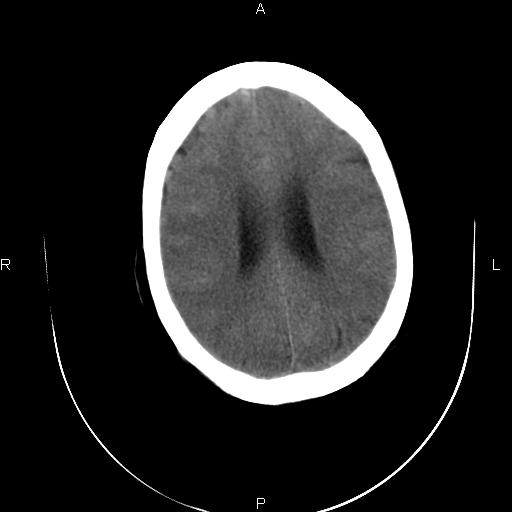

标题: CT20052:女76岁既往偶有头疼。

近三天来阵发性头剧疼 头晕加重。考虑蛛血?双额叶颅板下低密度是否为蛛网膜囊肿?请老师们指教指教!

2、脑萎缩,双额叶颅板下低密度为增宽的蛛网膜下腔。

2、双侧额部硬膜下积液;

2、脑萎缩,双额叶硬膜下积液。

蛛网膜下腔出血;双侧额部硬膜下积液;脑髓质萎缩。

1、蛛网膜下腔出血。

2、双侧额骨颅骨内板下的带状低密度影,不是增宽的蛛网膜下腔。依据:本病人本身有蛛网膜下腔出血,双侧额叶表面有一带状高密度影,那才是有出血的蛛网膜下腔。前面的带状低密度影(额骨内板下)是硬膜下积液表现,其内没有出血迹象,与出血的蛛网膜下腔界限清晰。